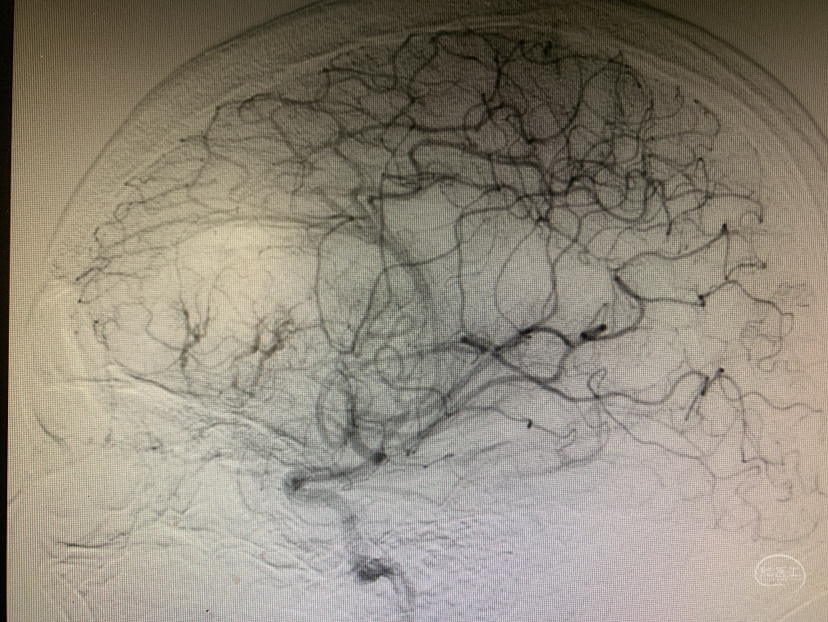

DSA(颈内造影)

DSA(颈外造影)